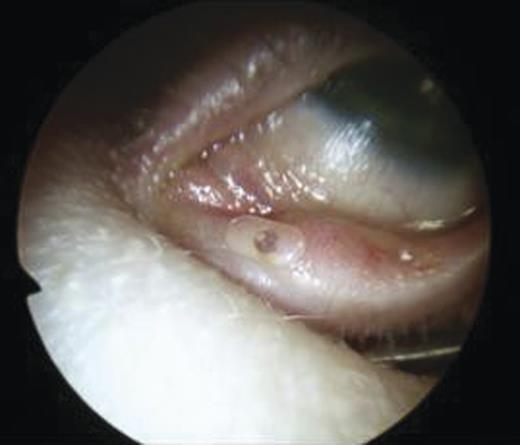

The puncti were probed (Fig. 5) and fluorescein dye instilled with no dye outflow to the left inferior meatus. It was not possible to pass the probe through the upper punctum so a mini-monoka DCR stent was inserted and secured (Figs. 6 and 7). Chloramphenicol eye drops were instilled.